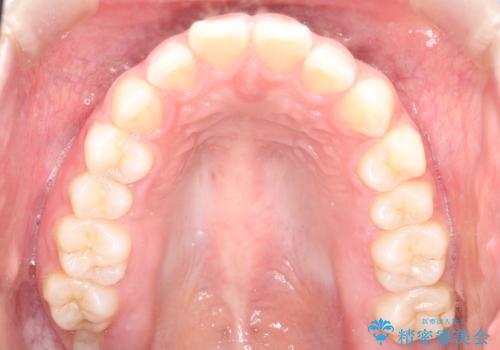

【インビザライン】出っ歯を引っ込めたい。

- 前歯の隙間と、出っ歯に見えることを主訴に来院されました。

できるだけ目立たない装置をご希望されましたので、インビザラインにて治療を行いました。

治療中は、できるだけ前歯を下げることができるように”顎間ゴム”を使用します。

”顎間ゴム”を利用することで、奥歯を後ろに動かす力を強めることができます。